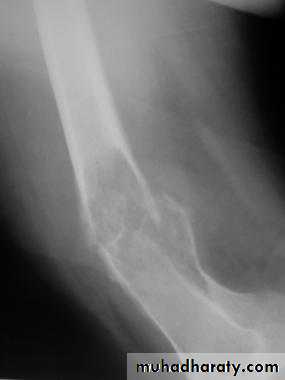

Supracondylar fractures of the femur

Typically the fracture occurs just proximally to the point where the medial and lateral cortices of the femur flare out to form condyles. In young it follow sever trauma and in old follow osteoporosis.

A vertical extension of the fracture may split the two condyles apart in a T – shaped fracture line, and sometime there is more extensive comminuation.

Treatment :

These fractures can sometimes be treated successfully by traction through the upper tibia in young, followed by cast brace.

In old internal fixation is often preferable and the patient can get out of bed sooner (dynamic condylar screw and plate) .

dynamic condylar screw and plate

Supracondylar fracture with its fixation by L – plate and screws